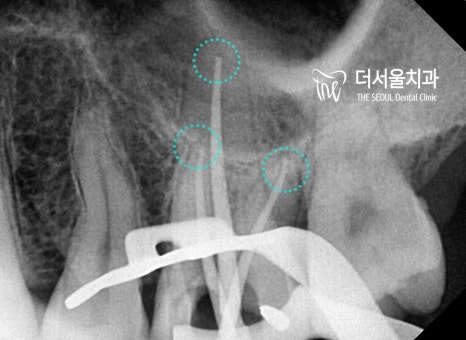

『엔도 크라운 진료 과정』

성남 치과에서는 앞서 계획했던대로

엔도크라운을 진행하기로 했습니다.

우선 감염된 근관을 깨끗하게

소독하고 세척하는 과정을 거쳤습니다.

우식이 꽤 깊은 곳까지 머물러 있었기 때문에

남은 병소가 없도록 확실하게 제거하는 것이

결과를 좌우하는 요소라 할 수 있죠.

어느때와 마찬가지로

꼼꼼하고 확실하게 도와드렸습니다.

뿌리 끝까지 근관충전을 마치고

코어 작업을 진행했습니다.